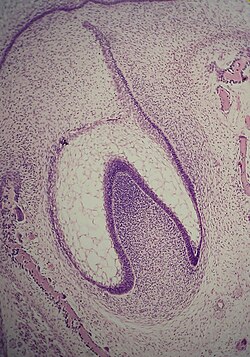

U stadiju kape započinje kalcifikacija caklinskog organa, proliferacija epitelnih stanica zametka u okolni mezoderm i invaginacija bazalnog dijela caklinskog organa.

U stadiju zvona se nastavlja proliferacija epitela i produbljivanje invaginacije u bazalnom području caklinskog organa. U udubljenje urasta mezoderm i formira dentalnu papilu, od koje će nastati zubna pulpa. Od mezenhimnih stanica razvija se folikularna vrećica, koja sa dentalnom papilom i caklinskim organom čini zubnu klicu.

Zubna pulpa sa periferno raspoređenim odontoblastima započinje stvaranje dentina (dentinogeneza), a caklinski organ pomoću ameloblasta stvaranje cakline (amelogeneza). Folikularna vrećica formira fibrovaskularnu kapsulu oko zuba u razvoju, koja je odgovorna za nutriciju, a ima i druge važne uloge. Na kraju stadija zvona počinje stvaranje kosti u mezodermu, folikul se transformira u periodontalno tkivo, a od caklinskog organa nastaje sekundarna dentalna lamina (za supstituentne zube). Također caklina i dentin formiraju zonu koja će postati caklinsko-dentinski spoj.